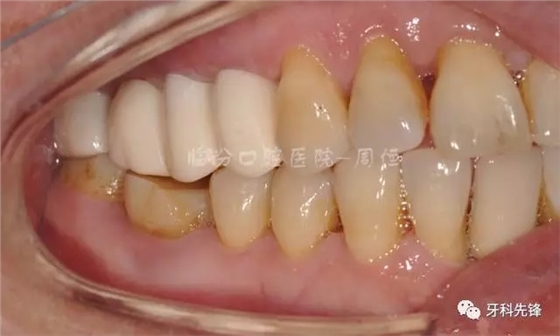

圖22烤瓷冠咬頜照

640.webp (26).jpg